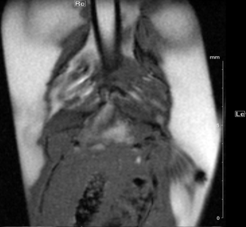

Physiological gating is required to minimize motional influence of the beating heart and respiration on the MR experiment but also to synchronize the imaging sequence to the cardiac cycle. Beside ECG electrodes and wires, a respiration sensor as well as tubings for inhalation and anaesthesia have to be kept within the probe head. In all measurements body temperature of the examined animal has to be maintained via thermostatically regulated water flow system. Currently it is possible to carry out all experiments necessary for the determination of the functional parameters of rat or mouse ventricles, like end-diastolic, end-systolic, and stroke volumes, ejection fraction, cardiac output, ventricular mass and wall-thickness within less than 45 minutes (Fig. 2).

Fig. 2: Mouse heart MRI. In the upper panel the endsystolic (a) and enddiastolic (b) phase of a mouse heart in the 4-chamber-view is displayed. In red: position of the 7 slices, orthogonal to the septum (1.0 mm thick, no gap). In the lower panel in (c) the endsystolic and in (d) the enddiastolic phase of an axial midventricular slice is shown. Note the papillary muscle.